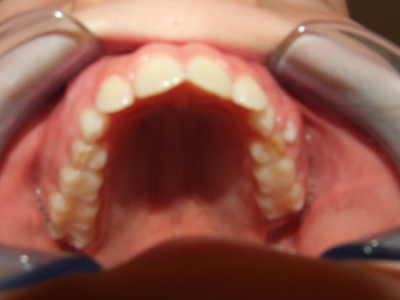

Leeftijd bij aanvang: 10 jaar

Bonded Hyrax + volledig vast onderkaak

Volledig vast bovenkaak + expander

Wrap + c-c bar onderkaak

Leeftijd bij afname: 12 jaar

Voor behandeling

Na behandeling